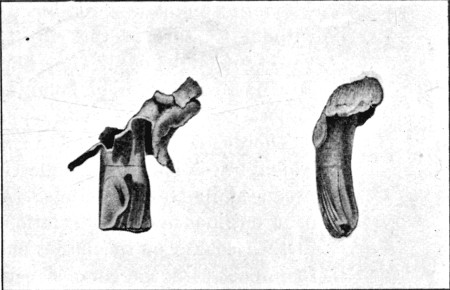

47. Explosive Exit Wound over Fractured Ulna156

48. Explosive Exit Wound over Fractured Humerus158

49. Explosive Exit and Entry Wounds of Legs159